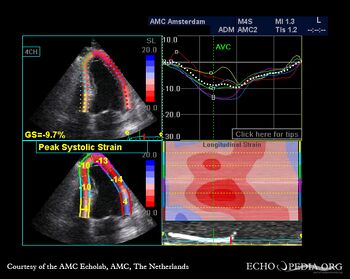

A4CH: akinesia of basal inferoseptal wall A2CH: akinesia of basal inferior wall

A3CH: akinesia of basal posterior wall A4CH: strain image

A2CH: strain image A3CH: strain image